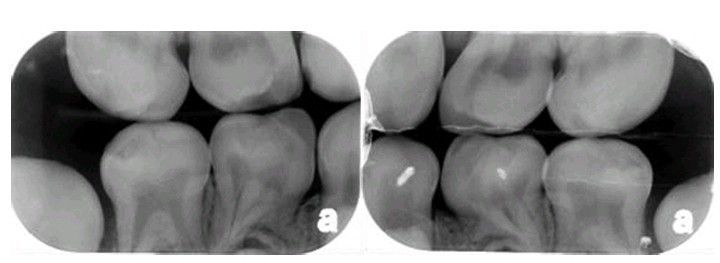

Globodontia. Bite-wing radiographs demonstrating posterior teeth with bulbous crowns and complex pulpal anatom